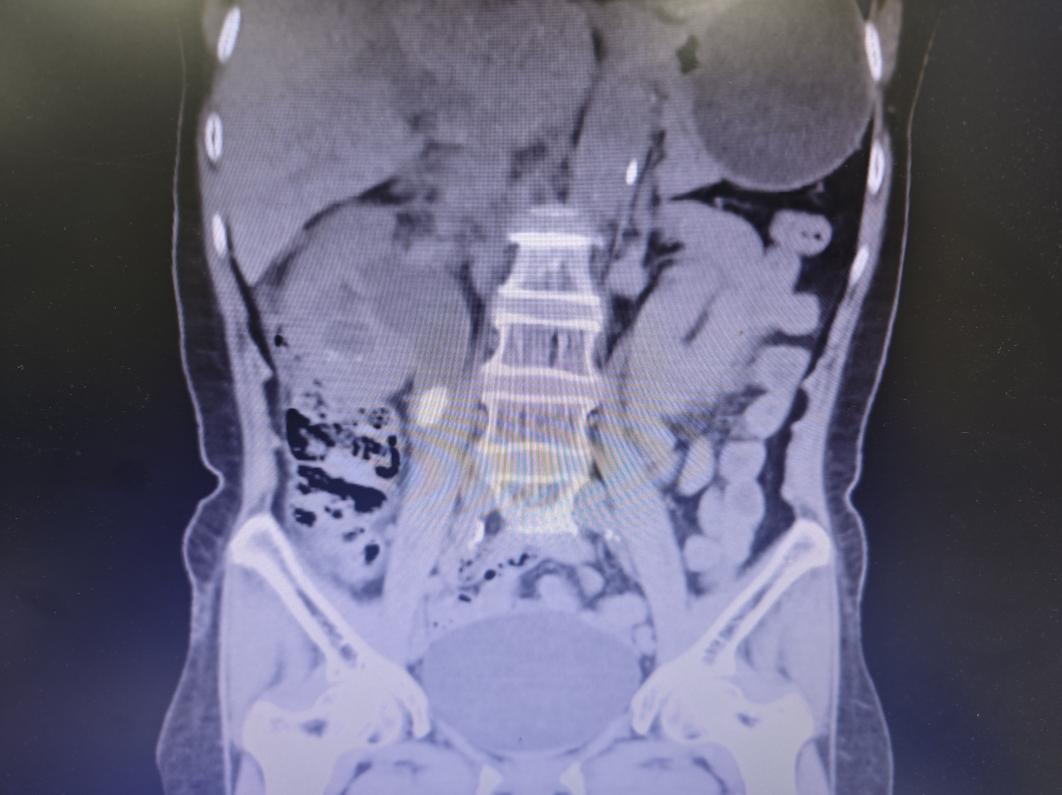

而泌尿系 CT 揭开了「元凶」——右肾结石堵塞了输尿管,导致尿液排不出去,细菌在里面大量繁殖,从而引发了 尿源性脓毒血症。「这是一种临床急危重症,进展迅猛,可导致感染性休克甚至多器官衰竭,尤其对糖尿病患者威胁更大!」

泌尿外科团队立即为刘阿姨实施急救处理,赵书晓主任医师为刘阿姨紧急留置右侧双「J」管作内支架置入引流,像给洪水开闸泄流,同步给予抗感染、降糖、补液等对症支持治疗。